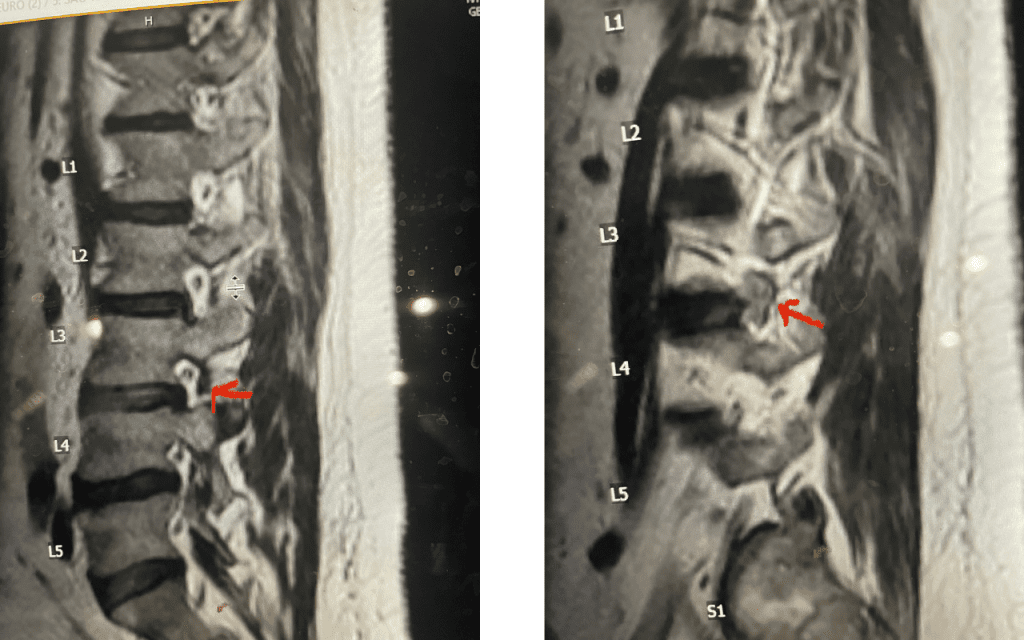

As an example of this type of pain syndrome, an interesting 58-year-old female presented with “soreness” and numbness of her left groin area for 6 months. She had no leg or back pain, weakness, or bowel or bladder dysfunction. She sought gynecological care, for which she had a pelvic examination. The examination elicited pain on left-sided palpation. She had negative imaging of her pelvis. Her family physician ordered a lumbar MRI, which revealed a left foraminal disc herniation compressing the left L1 root superiorly against the L1 pedicle (Fig 4). Clearly the numbness was in an L1 dermatomal distribution and correlated with the patient’s MRI. We started the patient on Medrol and Neurontin. We referred her to pain management for a left L1-2 transforaminal epidural and will follow her up in 6 weeks. If her problem does not resolve, we will offer surgical removal. It is important to realize that many patients with spinal pathology can present pain syndromes that mimic other conditions. For example, a patient may have an upper thoracic compression fracture with pain referred to the anterior chest wall, which can cause the patient to feel like they are having a heart attack. It is only during a cardiac workup that they discover the underlying problem with a chest x-ray.

Fig 4: Axial and Sagittal T2-weighted lumbar MRI demonstrating a left lateral foraminal disc herniation (red arrow) causing compression of the exiting L1 nerve root against the undersurface of the pedicle of L1.